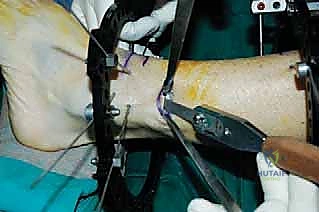

المرحلة الثانية: تركيب المثبت الخارجي (Frame Application)

قبل قطع العظم، يقوم الدكتور هطيف بتركيب الهيكل الخارجي (الإليزاروف أو الفريم الدائري).

1. يتم إدخال أسلاك دقيقة جداً (K-wires) ومسامير نصفية (Half-pins) عبر الجلد إلى العظم بدقة متناهية لتجنب الأعصاب والأوعية الدموية.

2. يتم تثبيت هذه الأسلاك في الحلقات المعدنية الخارجية. حلقة أو حلقتين فوق مكان القطع المخطط له، وحلقة تحته (في الجزء السفلي من الساق والقدم إذا لزم الأمر).

3. يتم التأكد من استقرار الهيكل الخارجي بالكامل.

المرحلة الثالثة: قطع عظمة الشظية (Fibular Osteotomy)

للسماح للظنبوب (العظمة الرئيسية) بالتحرك والتصحيح، يجب أولاً قطع عظمة الشظية. يتم ذلك عبر شق جراحي صغير جداً (حوالي 1-2 سم) في الثلث السفلي أو الأوسط من الساق.